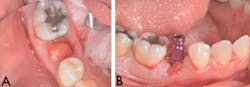

The surgical guide was placed, and a full seat was observed with good stability (figure 8A). The osteotomy site was prepared using serial drills per manufacturer’s recommendation (figure 8B).

Puros Demineralized Bone Matrix Putty (Zimmer Biomet) was used to fill in the gap between the implant and the socket and to repair the midbuccal fenestration (figure 9A). (3–4) A 4.7-mm x 11.5-mm Zimmer Trabecular Metal implant (Zimmer Biomet) was placed (figure 9B). The implant appeared to have good primary stability, ~45 Ncm.